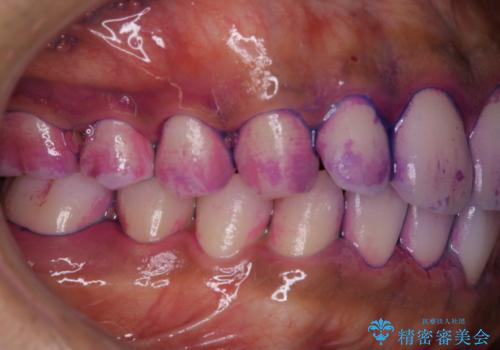

- 特に症状など気になるところはないが、メンテナンスして欲しいとのことでした。染め出しをしてのブラッシング指導とPMTC30分コースを行いました。

染め出しをすると、現在付着しているプラークを確認できて、今後の正しいハミガキの方法を知るチャンスとなります。